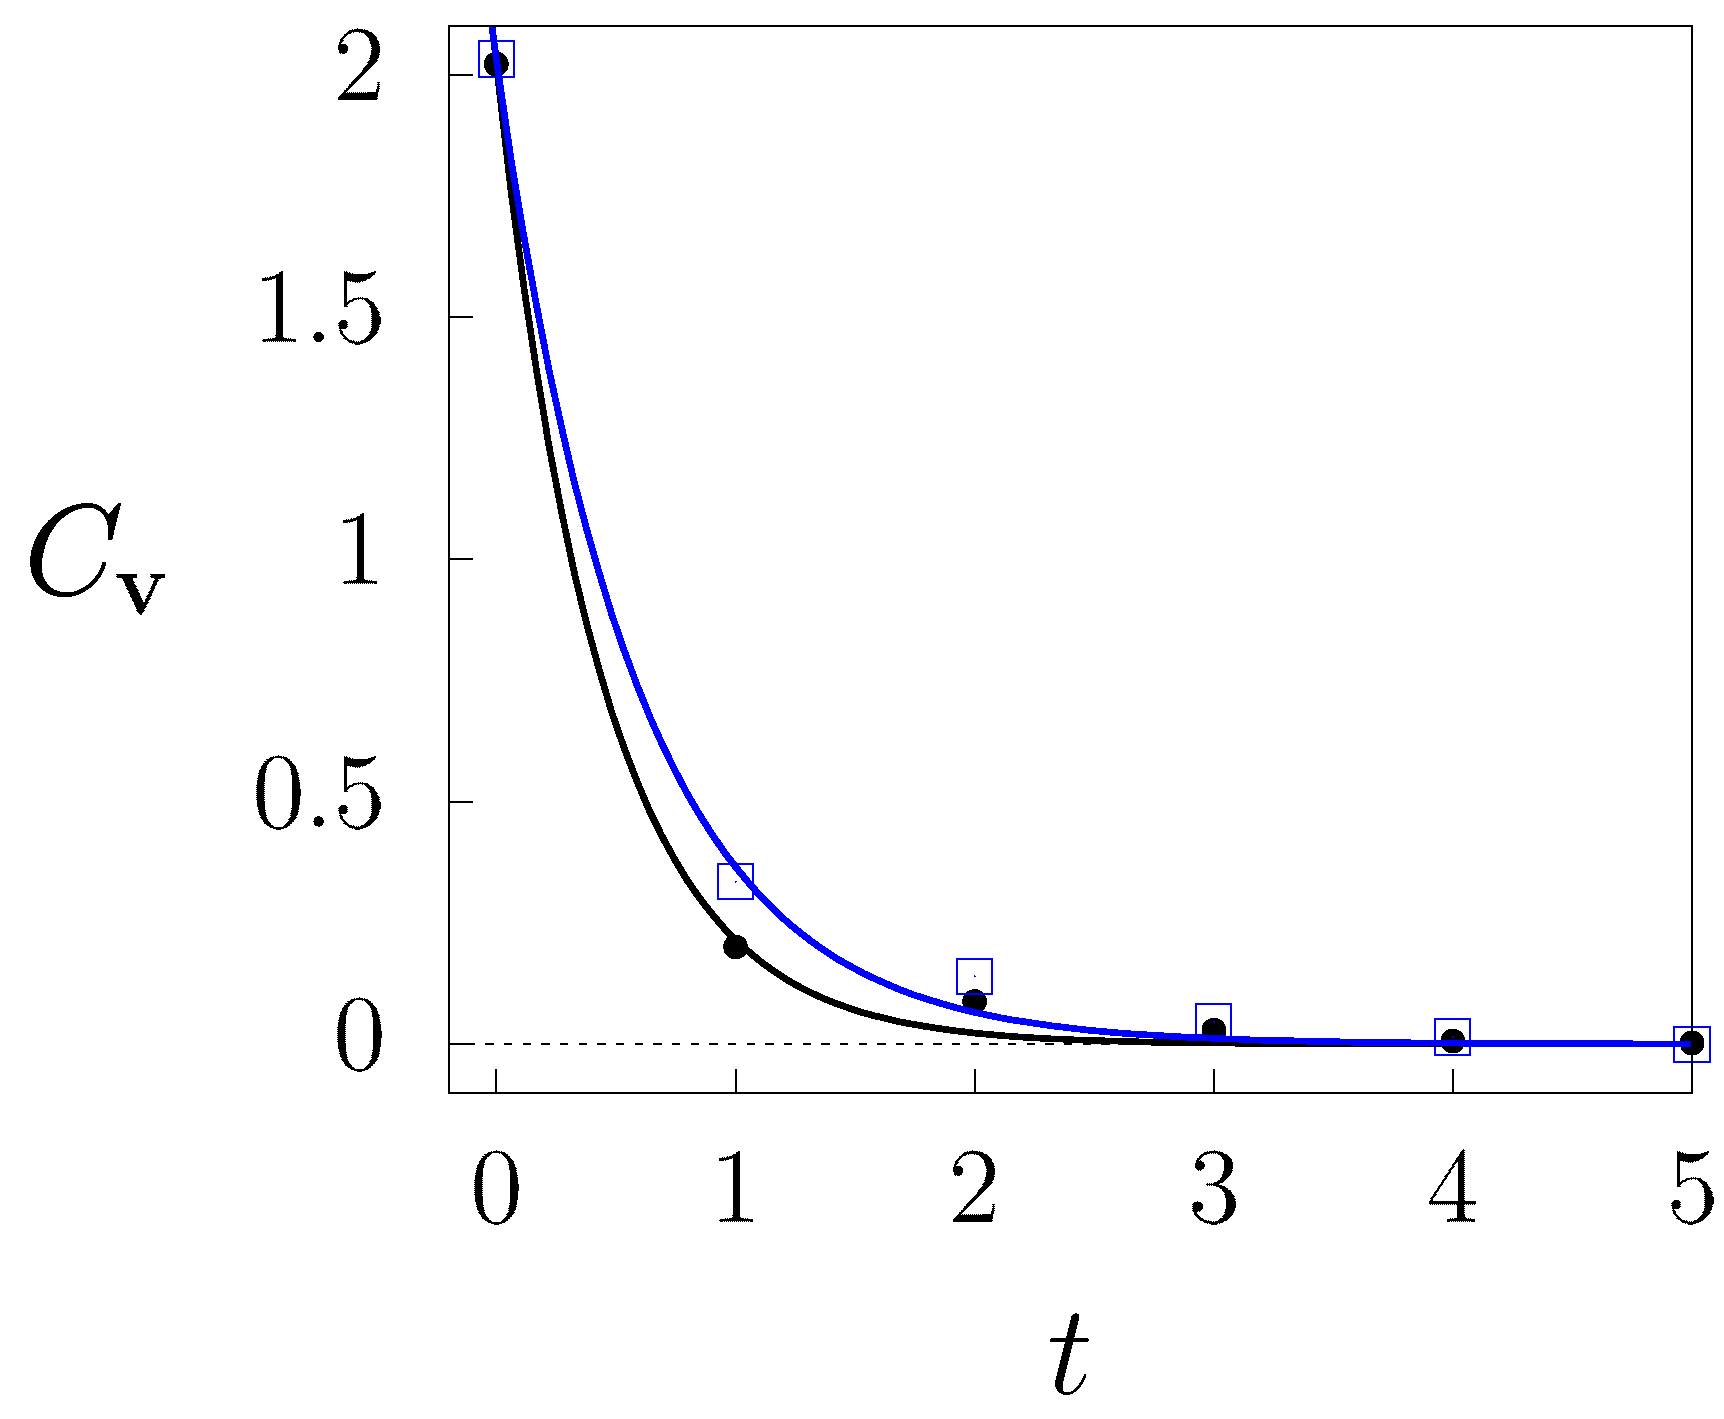

2. MDC Calculation

2.2. Mesoscopic Technique